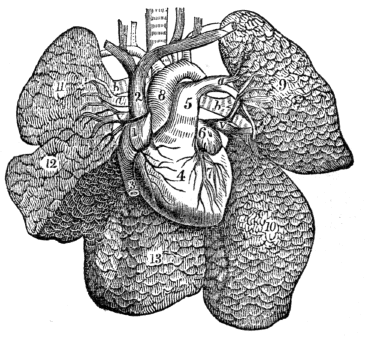

| 17. | Anatomy of the Circulatory Organs, | 154 |

| 18. | Physiology of the Circulatory Organs, | 164 |

| 23. | Anatomy of the Respiratory Organs, | 209 |

| 24. | Physiology of the Respiratory Organs, | 217 |